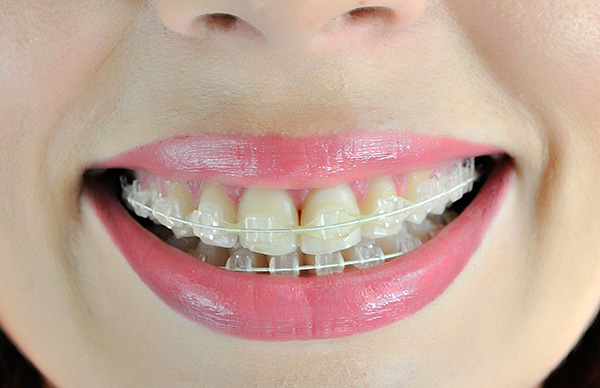

La foto sotto mostra le parentesi graffe dello zaffiro:

Per coloro che, quando correggono il morso, non vogliono che l'ambiente circostante veda le parentesi graffe in bocca, ci sono 2 sistemi.